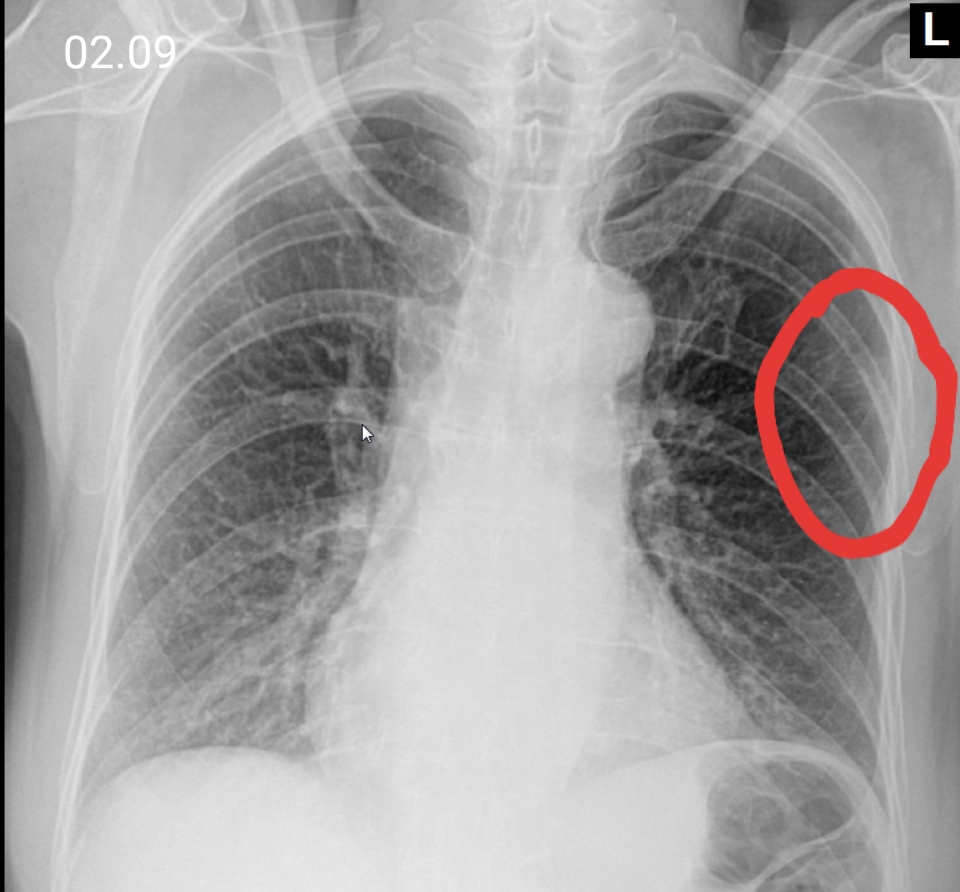

Медицинские аспекты заболеваний: рентгенологическая картина туберкулеза костей

Раздел: Снимки-откровения